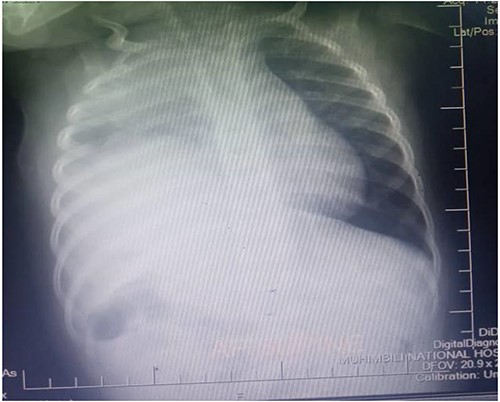

A one-year-old female child was admitted in Emergency Department after being involved in a motor traffic crash as a passenger where she sustained injury to the right leg and blunt head-thoracic-abdominal trauma. After resuscitation and supportive therapy, she underwent plain chest x-ray, which showed reduced right lung volume with elevated right hemidiaphragm and right upper zone opacity. The cardiac silhouette was obliterated in the right.

Figure 1 shows the plain chest radiography demonstrating the right lung atelectasis with elevated right hemidiaphragm and obliterated cardiac silhouette taken before laparotomy.